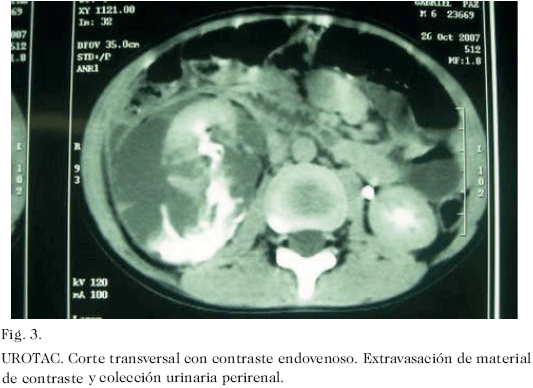

Escolar masculino de 6 años de edad quien acudió a la emergencia del Hospital Universitario de Maracaibo, 1 hora posterior a presentar contusión lumbar derecha al caer sobre su altura, que ocasionó dolor local de fuerte intensidad y hematuria macroscópica. El examen físico reveló paciente en regulares condiciones generales, con moderada palidez cutáneo-mucosa, pulsos periféricos débiles, 139 pulsaciones y 32 respiraciones por minuto. La valoración abdominal evidenció dolor a la palpación desde hipocondrio hasta fosa iliaca derecha, con contractura muscular voluntaria. Se indicó expansión vascular con solución de Ringer Lactato, a razón de 20 mL kg/peso. Sus condiciones hemodinámicas se mantuvieron estables. Se indicó hidratación de mantenimiento. La hemoglobina descendió 3,1 g% en las primeras 48 horas. Se indicó concentrado globular cuando las cifras de hemoglobina descendieron hasta 6,8 g%. Se realizó eco-doppler renal al ingreso en la emergencia que reportó compromiso de parénquima derecho con presencia de flujo vascular y colección peri renal (Fig. 1). Se practicó tomografía computadorizada simple 10 días posteriores al ingreso; en los cortes sin contraste (Fig. 2), se comprobó la colección observada en el ecograma. Cuando se administró contraste endovenoso, se evidenció extravasación del material de contraste al espacio retroperitoneal derecho (Fig. 3). A los 16 días del accidente se drenó el urinoma en quirófano con un nefrostomo percutaneo calibre 14 Fr. en región lumbar derecha no dirigido por ultrasonido ni tomografía, obteniéndose un litro de orina. La evolución clínica fue satisfactoria, egresando una semana después con catéter de drenaje. A los 43 días del accidente y a los 27 días de haber colocado el nefrostomo, se retiró en quirófano. Seis meses posteriores al traumatismo el paciente se encuentra sin síntomas y libre de complicaciones. En la urografía de eliminación realizada 4 meses posteriores al trauma, se observó parénquima renal funcionante, con leve alteración de arquitectura del sistema urinario excretor y buena eliminación a través del mismo (Fig. 4).